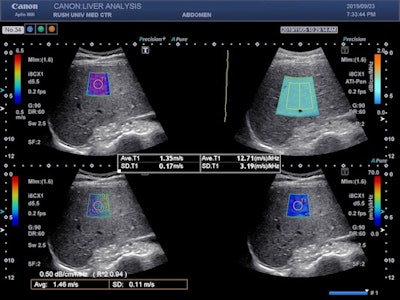

In other ultrasound developments, Canon has rolled out software on Aplio i-series scanners designed to help users determine cutoff values for shear-wave elastography scans to determine liver stiffness in assessments of compensated advanced chronic liver disease (cACLD). The software displays the calculated measurement averages from multiple samples of the liver, and it is customizable based on the "rule of four" guidelines issued by the Society of Radiologists in Ultrasound.

Image shows the Aplio i-series liver analysis technologies (shear-wave elastography, attenuation imaging, and shear-wave dispersion) and propagation map acquired simultaneously in real-time.The system offers data on standard deviation and interquartile range (IQR), in addition to a visual propagation map, that helps users ensure accurate and confident application of the "rule of four" to determine cACLD and for the assessment of other liver pathologies.